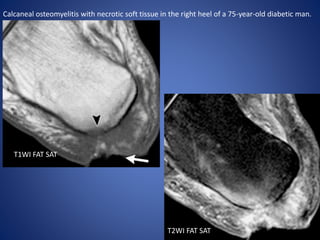

Calcaneal osteomyelitis with necrotic soft tissue in the right heel of a 75-year-old diabetic man.

T1WI FAT SAT

T2WI FAT SAT

Calcaneal osteomyelitis withnecrotic soft tissue in the right heel of a 75-year-old diabetic man. T1WI FAT SAT T2WI FAT SAT

• #23 (a, b) Axial T1-weighted (a) and T2-weighted fat-suppressed (b) MR images of the posterior calcaneus show a region of bone marrow edema (arrowhead in a) underlying a draining skin ulcer (arrow in a), findings indicative of osteomyelitis.

• #24 (c) Axial contrast-enhanced T1-weighted fat-suppressed MR image demonstrates a region of enhancing but viable bone in the posterior calcaneus, with a large area of nonenhancing soft tissue (*) representing overlying necrosis. The nonviable soft tissue was sharply débrided, and antibiotic therapy was initiated.